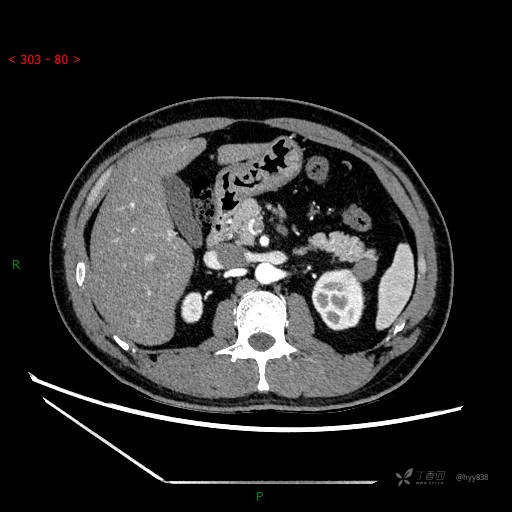

胰腺CT平扫

增强动脉期

增强静脉期

CT值

42hu 48hu 57hu